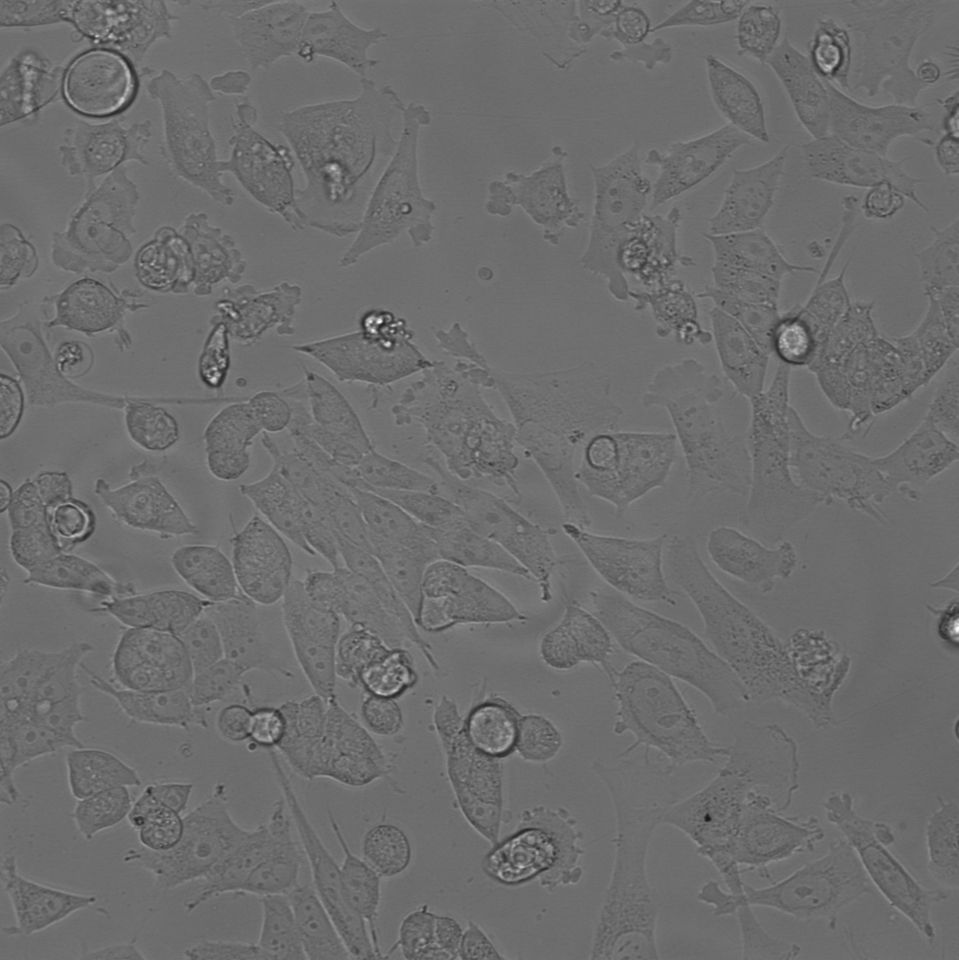

细胞名称:DMS 273 _人小细胞肺癌细胞

生长特性:贴壁生长

细胞形态:梭状

培养条件:Waymouth's MB 752/1 + 2mM Glutamine + 10% FBS (Heat Inactivated) + 1%P/S,37 ℃, 5% CO2